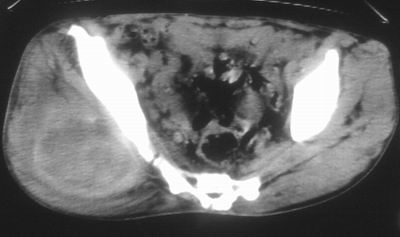

标题: CT16837:M63Y,右臀部巨大软组织包块 [打印本页]

标题: CT16837:M63Y,右臀部巨大软组织包块

患者,男,63岁,自诉3个月前发现右臀部包块,触及疼痛,治疗后缩小。前天突然增大。无高热病史。

考虑-----右臀大肌,臀中肌---感染性病变可能性大。

恶性软组织肿瘤可能性不大

病灶内部可见出血,首先考虑急性出血性病变.血肿?

给个骨窗,判断一下肿块是否与髂骨有关,肿块内出血是肯定的,至于是感染形成的脓肿还是起源于肌肉或纤维组织的肉瘤则难以确定,不过从影像上看,包膜完整,且环形增厚,病灶下部见斑片状底密度坏死,个人倾向感染可能性大

肌间隙明显混浊,三个月前治疗有缩小,支持考虑臀大肌下脓肿伴出血,肿瘤如果出现瘤内出血的话瘤外边界应该较清楚,现在表现为一种恶性征像,但骨质无明显异常,且臀小肌边界清楚,不符合恶性表现.